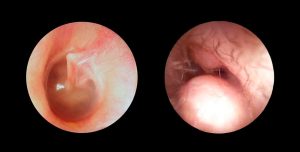

O que é colesteatoma?